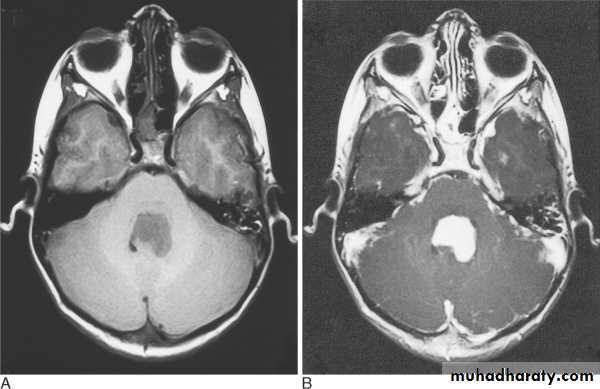

PD T2 T1

Sagittal coronal